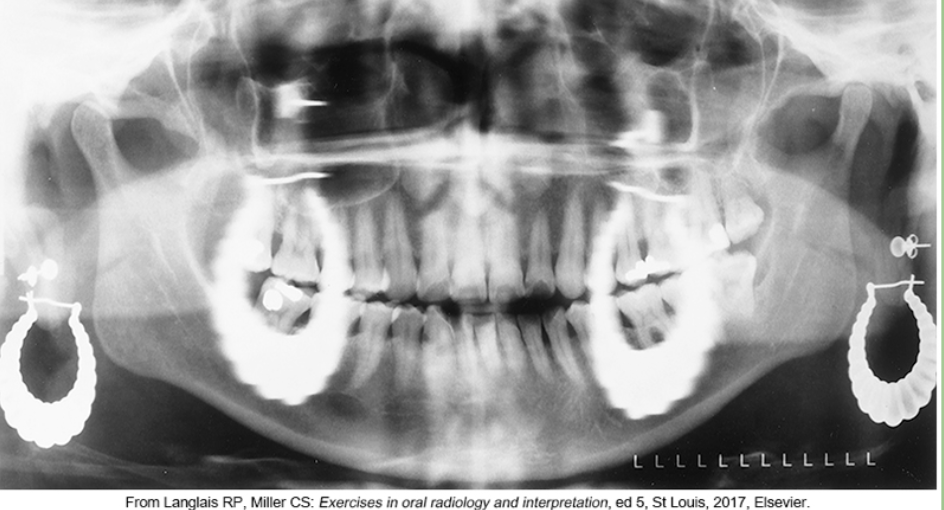

whats the problem

wearing earrings